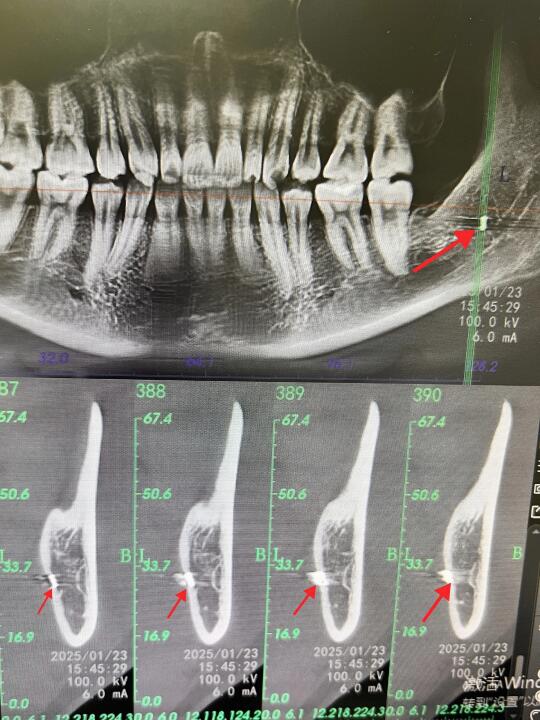

👨🏻⚕️今天有个美女过来找锤哥拔牙~ 👨🏻⚕️美女说有上次在诊所拔牙的牙片,锤哥看后说“还是在我们科重新拍一张牙片吧~” 🤣不拍不知道,一拍吓一跳,拍片后发现美女上次拔牙后,骨头里有个高密度影~ 👨🏻⚕️以锤哥多年的工作经验来看,这好像是折断在里面的「钻头」 🫣好在锤哥先复查了一个牙片,不然还真有点说不清了,话说那个诊所也是🐮B,骨头里留下这么长一根钻头,都不跟患者说,也不想办法取出来~ 👨🏻⚕️锤哥在这里奉劝大家,拔牙风险高,且拔且小心❤️啊!